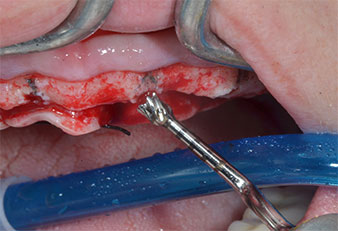

Un insert piézoélectrique diamanté de forme effilée (Piezomed I1) a été utilisé pour marquer les positions implantaires et effectuer la préparation pilote (Fig. 3). On a pris soin de travailler selon un mouvement ascendant et descendant, à puissance réduite, irrigation complète et basse pression (moins de 300g). Ensuite, un insert pilote (Piezomed I2A/I2P) a été utilisé pour l’agrandissement initial de 2mm du diamètre des sites implantaires (Fig. 4), suivi d’un insert de 3mm (Fig. 5).

En cas de densité osseuse élevée, il convient d’utiliser toute la gamme d’inserts, y compris les inserts intermédiaires Piezomed Z25P et Z35P afin d’élargir

les ostéotomies avant l’étape d'agrandissement suivante.

Dans le cas présent, les inserts Z25P et Z35P n’ont pas été utilisés car l’os postérieur était relativement mou

et l’intervention sur celui-ci a été aisée avec le I3A/I3P.